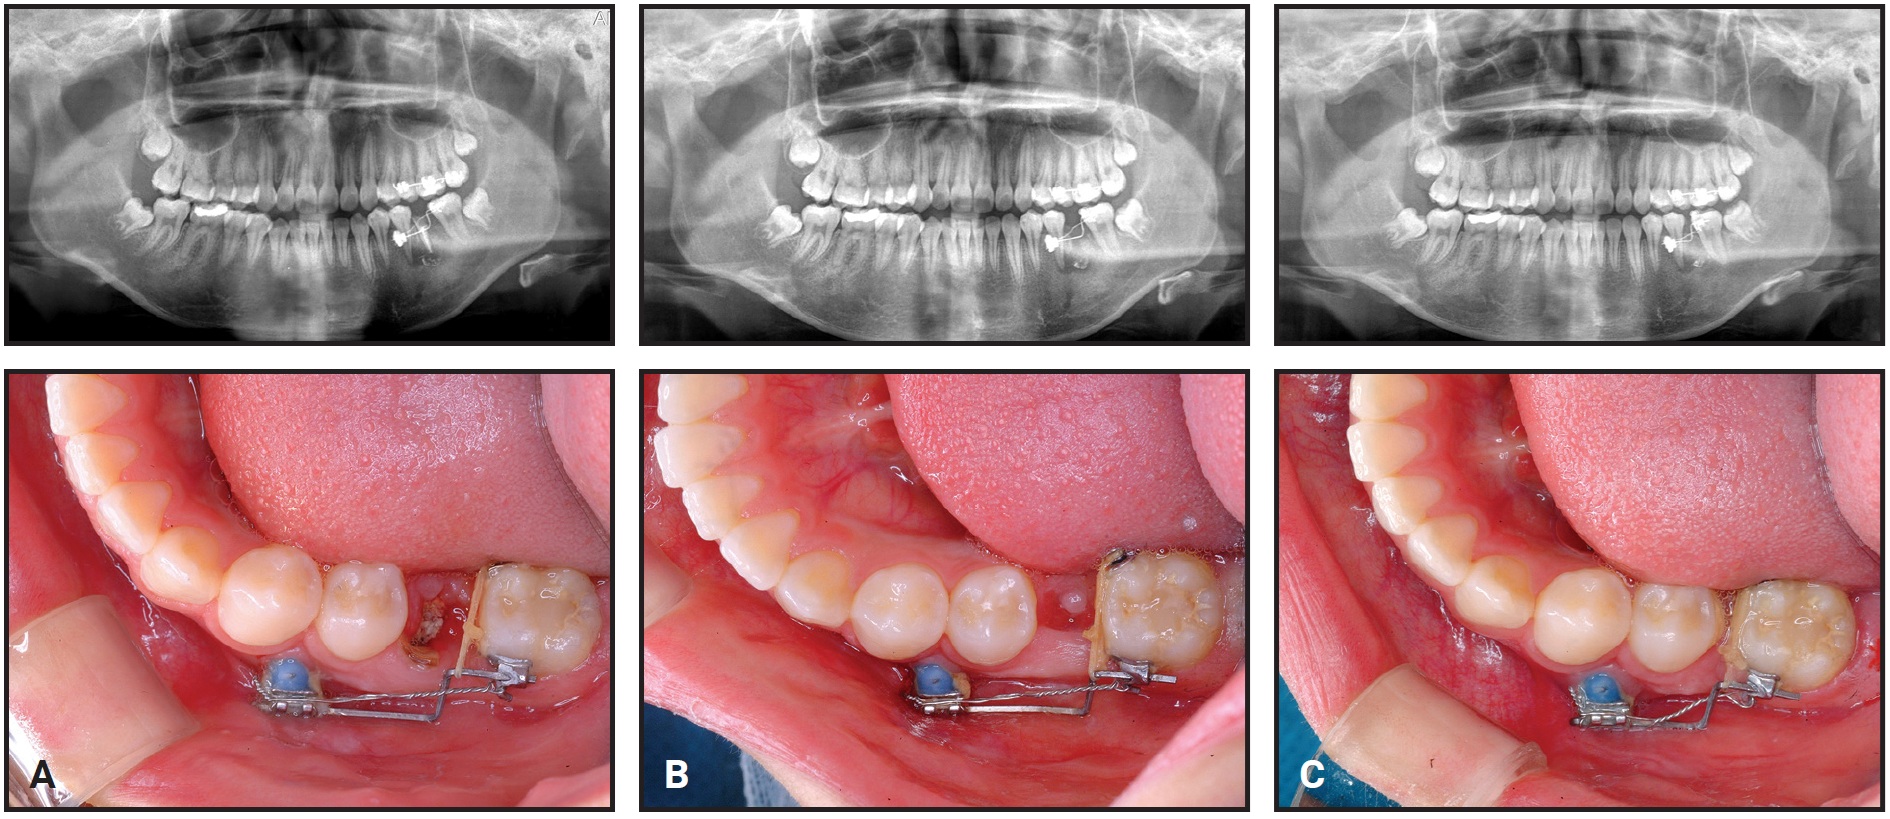

A 15-year-old female presented with a hopeless lower left first molar with periapical pathosis (Fig. 1).

Fig. 1 Case 1. 15-year-old female patient with hopeless lower left first molar before treatment.

She was referred for extraction of the first molar and protraction of the second and third molars to close the space. To minimize the risk of alveolar bone atrophy, the first molar was hemisected, and only the distal root was extracted before orthodontic mechanics were initiated.

Two small-headed, 6mm micro-implants* were placed into the buccal alveolar bone between the lower left first and second premolars (Fig. 2A). The micro-implants were tied together with stainless steel ligature wire and built up with composite resin. A standard .018" upper-incisor bracket was bonded to the composite (Fig. 2B), a tube was bonded to the lower second molar, and an .017" × .025" TMA** sectional wire was inserted to connect the bracket and tube.

Fig. 2 Case 1. A. Two micro-implants* placed between lower left first and second premolars and built up with composite. B. Bracket bonded to composite and connected to second-molar tube with TMA** sectional wire.

The ligature wire was tightened every four weeks for reactivation.

We decided to protract the second molar with slight intrusion to facilitate tooth movement. To prevent extrusion of the upper molars, brackets were bonded and a sectional wire was placed.

The lower second molar was slightly intruded by the sectional archwire, taking it out of occlusion (Fig. 3).

Fig. 3 Case 1. A. After two months of treatment, with first-molar mesial root remaining. B. Mesial root of first molar extracted after three months of treatment. C. After nine months of treatment, edentulous space almost closed.

After three months of protraction, the space created by extraction of the distal root was closed, and the mesial first-molar root was extracted. To prevent mesial tipping of the second molar, a tipback bend was made in the TMA wire. After nine months of treatment, the space was almost closed.

The third molar spontaneously moved mesially, following the protracted second molar. A gingivectomy was performed on the third molar, and a bracket was bonded for uprighting. After 16 months of treatment, the second and third molars were aligned into occlusion (Fig. 4).

Fig. 4 Case 1. A. Spontaneous mesial movement of third molar after 13 months of treatment. B. Three months later, molars aligned into occlusion.

After six months of retention, the micro-implants were removed (Fig. 5).

Fig. 5 Case 1. After six months of retention, favorable occlusion observed and micro-implants removed.

Records showed a well-maintained occlusion without root resorption or alveolar bone loss. The teeth displayed almost bodily movement without tipping, and no side effects, including alveolar bone atrophy, inflammation, soft-tissue clefting, or root resorption, were observed.